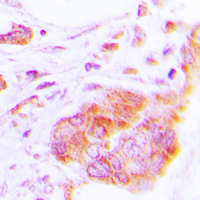

Immunohistochemical analysis of COX17 staining in human lung cancer formalin fixed paraffin embedded tissue section. The section was pre-treated using heat mediated antigen retrieval with sodium citrate buffer (pH 6.0). The section was then incubated with the antibody at room temperature and detected using an HRP conjugated compact polymer system. DAB was used as the chromogen. The section was then counterstained with haematoxylin and mounted with DPX. -